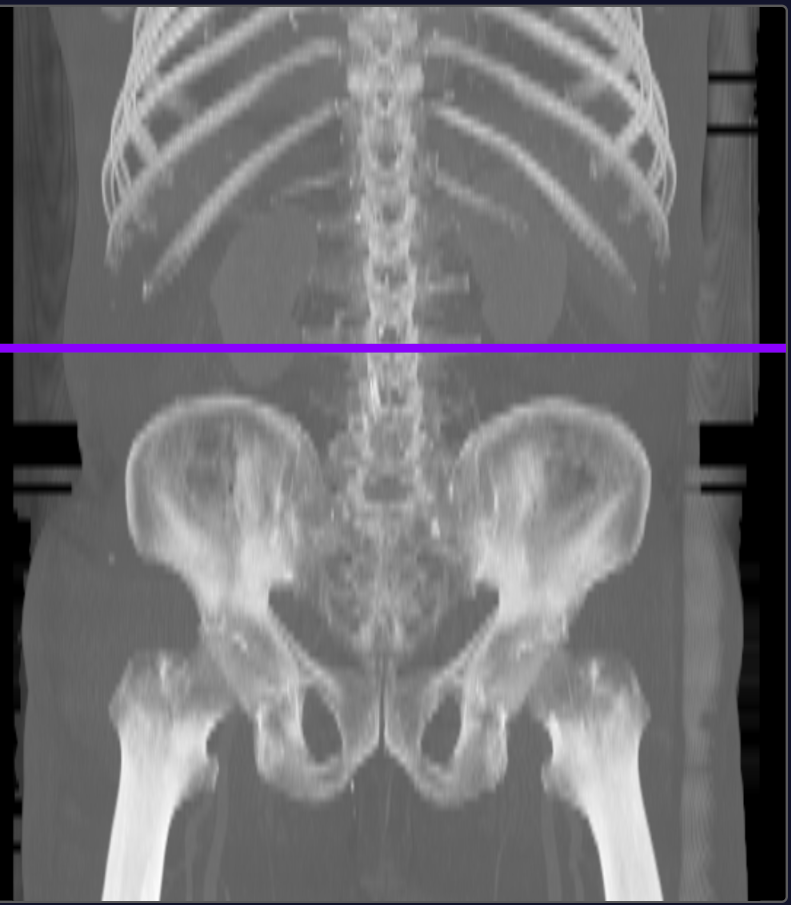

정확한 위치 찾기가 어려웠습니다

CT 영상에서 L3 척추 레벨을 정확히 찾는 것은 전문가도 어려운 일입니다. 사람마다 척추 모양이 다르기 때문이죠.

AI가 자동으로 L3 위치 찾기

L3 자동 인식